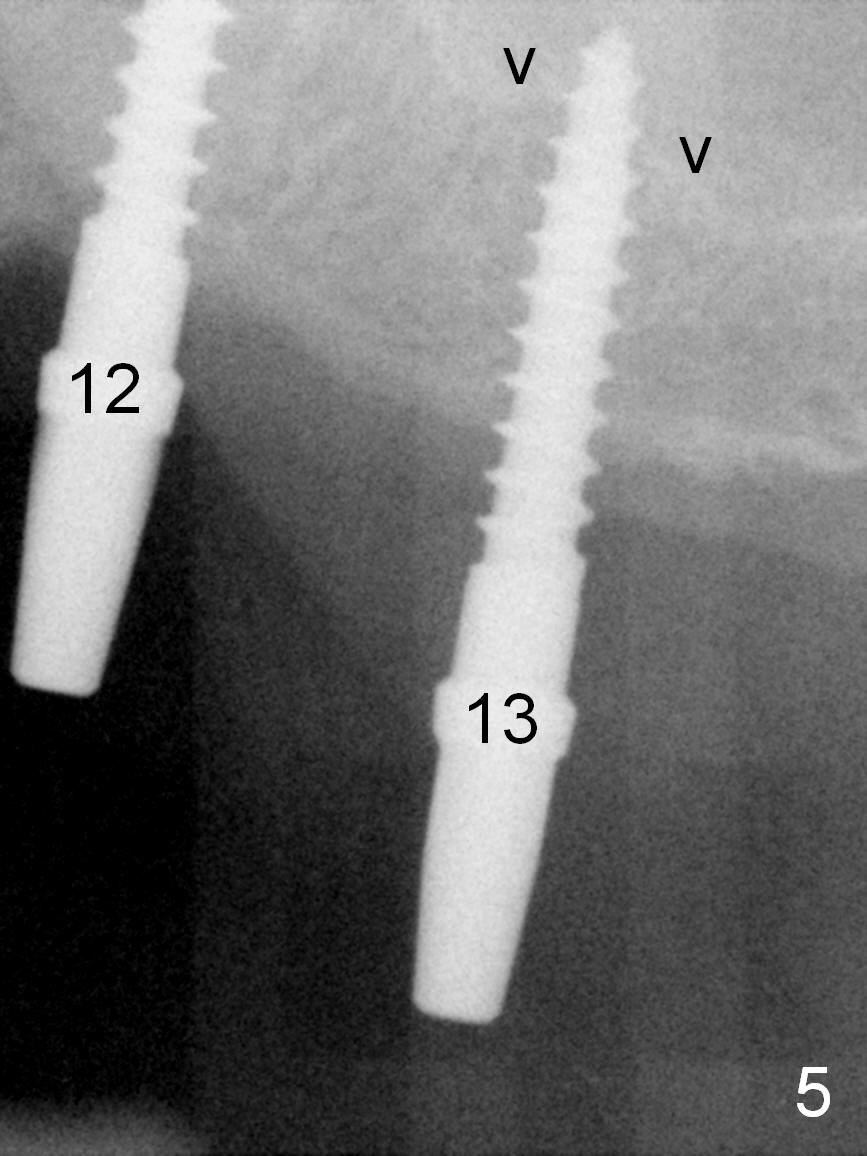

When the patient returns for implant placement (2nd visit after initial exam), he reveals that he is a dental phobic.  He requests placement of 4 implants in the upper left quadrant, instead of 2.  Narrow ridge is unexpected in the canine and premolar area (Fig.1).  Limited bone height at #13 (Fig.3 arrowheads: sinus floor) is found when initial drills are in place (Fig.2,3).  A 2-piece implant (4.5x17 mm tissue-level) is placed at #10 after extraction, while 1-piece implants are placed at 11 (3x17 mm (tissue-level, 15 °) and 12 and 13 (bone-level, 2.5x14, 12 mm, respectively; Fig.4,5).  In fact the 1 piece implant at #13 is not completely placed (Fig.5).  It is removed, the apical 3 threads are cut off (Fig.6 <, since a shorter implant was unavailable in the office) and the remaining implant is re-inserted.  The insertion torques of the 4 implants are ~ 60, ~ 35, < 35 and 15 Ncm, respectively.  After adjustment (Fig.7), immediate provisionals are fabricated at #10 and 11 (Fig.8, later splinted with composite), while perio dressing is applied around the implants at #12 and 13 and the provisionals at #10 and 11.  There is no nasal hemorrhage postop.  Although the perio dressing is loose 1 week postop (Fig.9), it is not removed.  When the upper lip fissure (Fig.9 <) heals, provisionals at #12 and 13 are planned to be splinted to the other two ones.  Two weeks postop, the upper lip fissure heals, the perio dressing dislodges and the implants at #12 and 13 are stable (Fig.10).  After abutment height adjustment, a splinted provisional is fabricated over these 2.5 mm 1-piece implants (Fig.11).